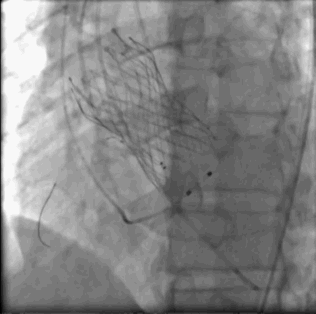

瓣膜释放完成左右冠显影良好撤出保护

瓣膜最终形态

术后患者早期脱机,心电图:窦性心律,一度房室传导阻滞,左束支传导阻滞。复查床旁彩超无明显瓣周漏。术后7天出院。术后用药:阿托伐他汀、阿司匹林、氯吡格雷、螺内酯。术后一月复查,心功能2级,心电图窦性心率,PR间期略延长。心脏彩超未见明显瓣周漏,瓣膜开放良好,无明显压差。